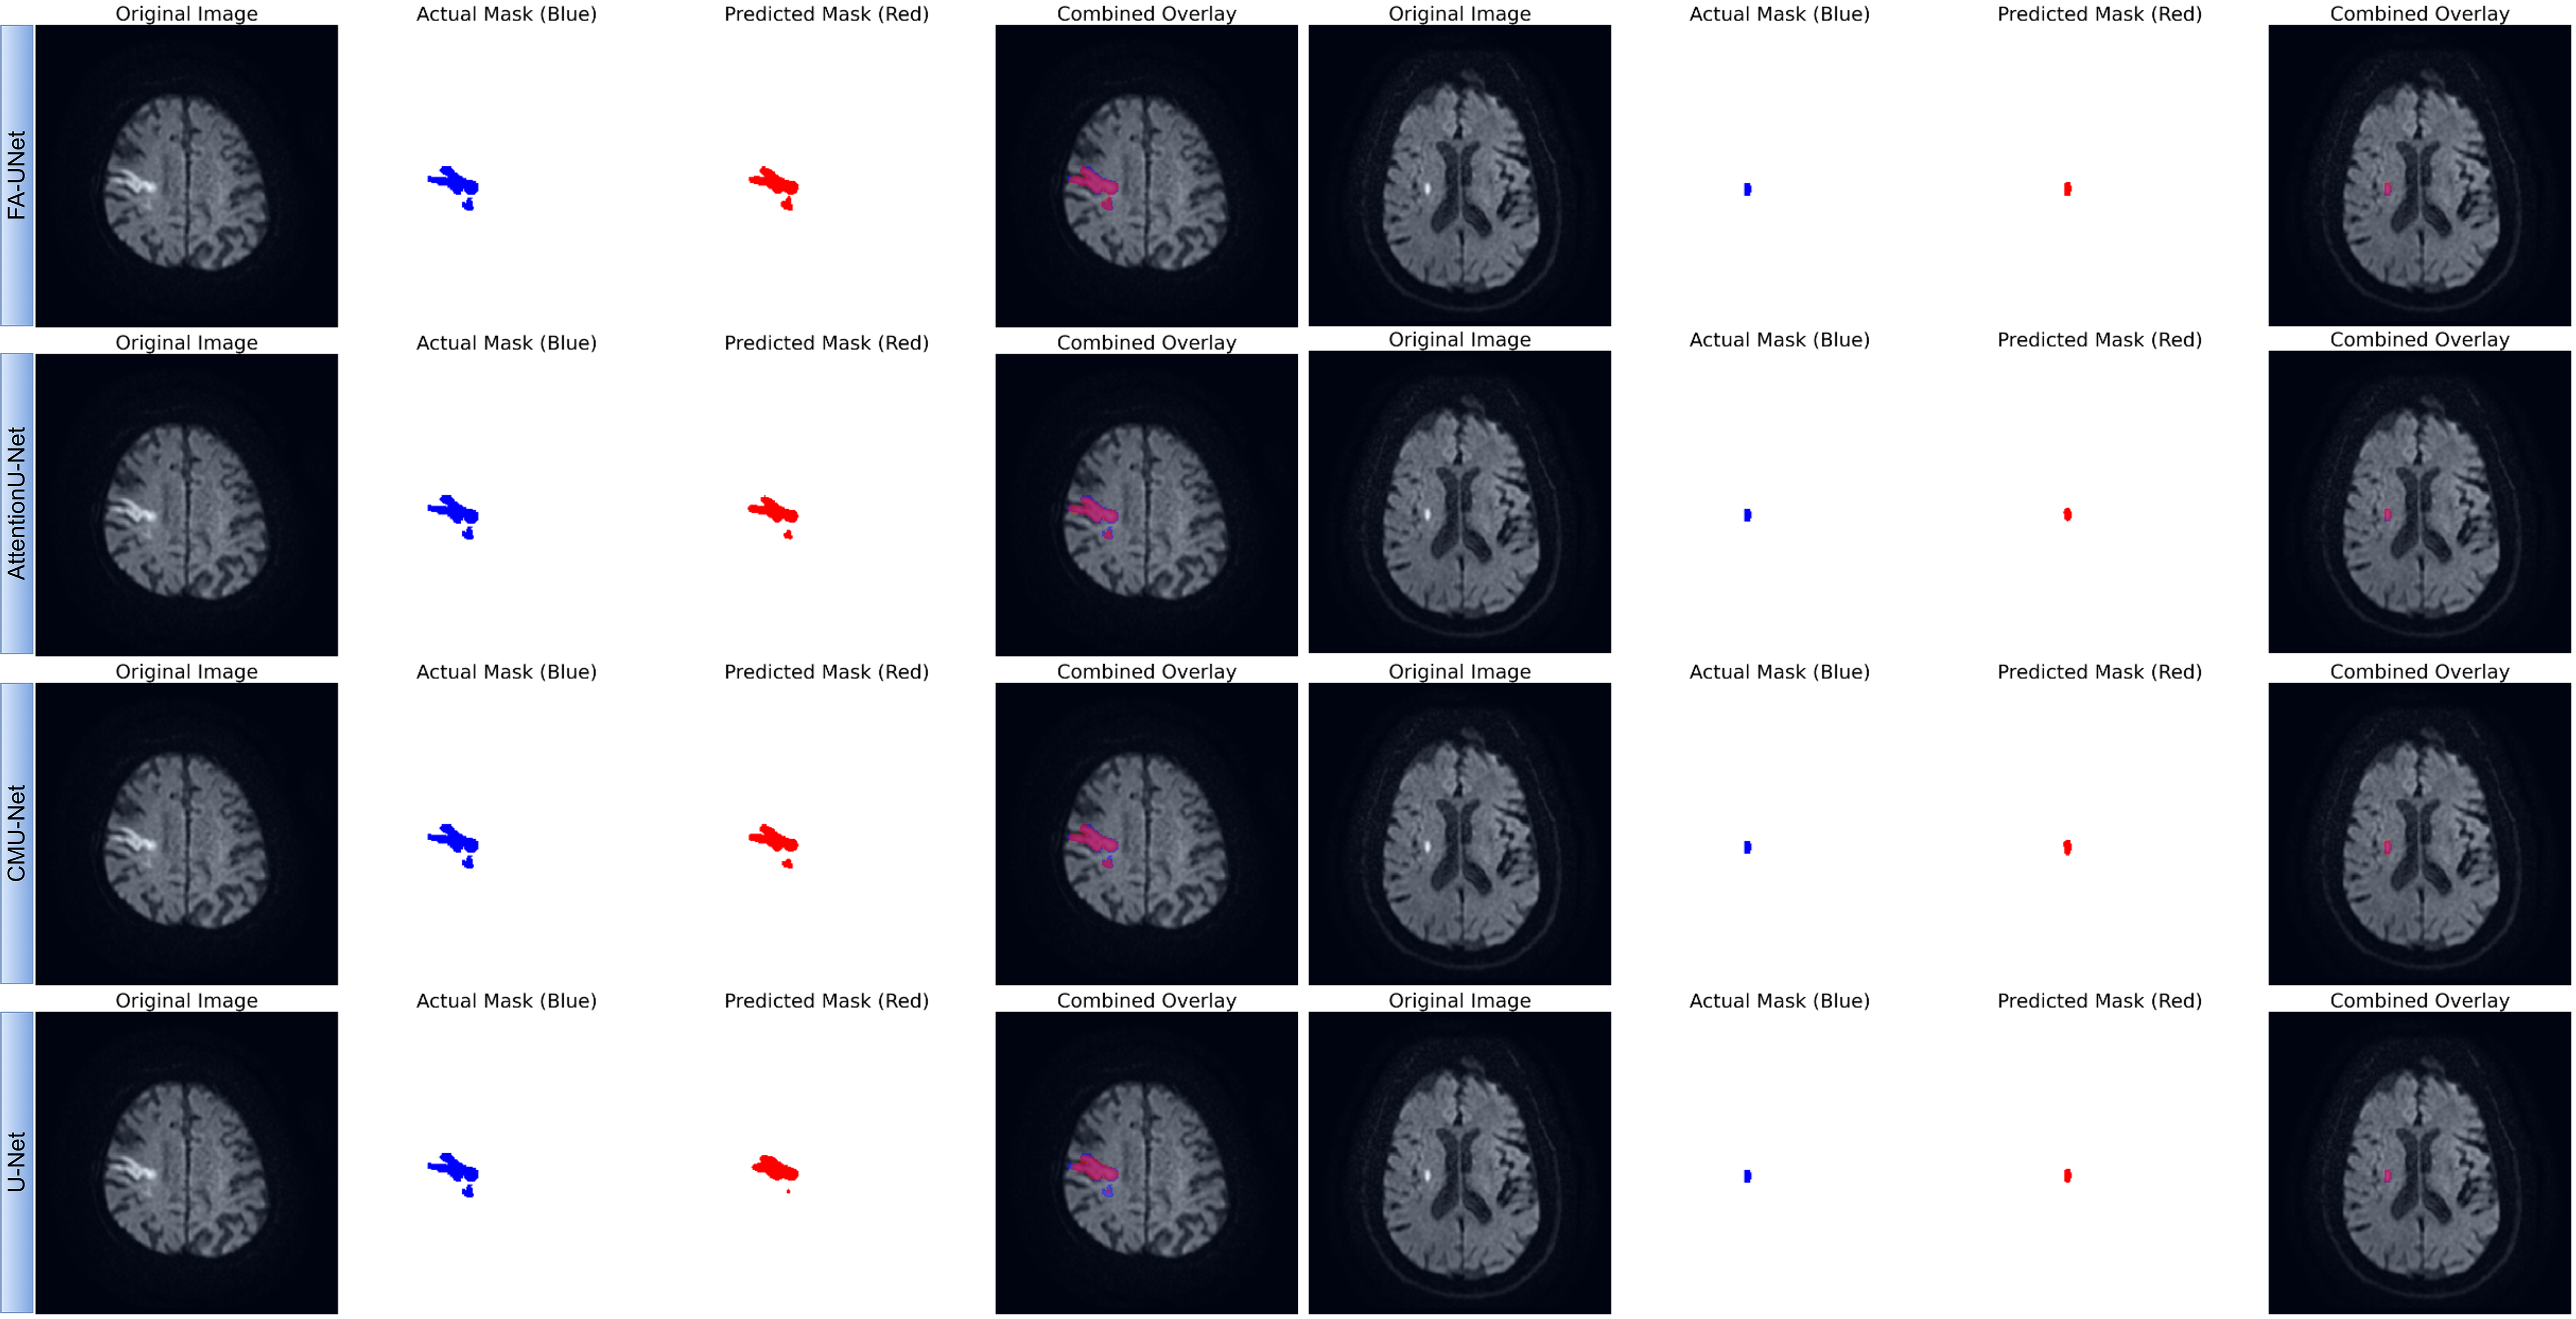

Fig. 4.

Qualitative comparison of segmentation performance for FA-UNet and benchmark models. The figure presents segmentation results on two representative cases from the test set: a large, morphologically complex lesion (left panel) and a small, well-defined lesion (right panel). For each model, the predicted mask (red) is compared against the ground truth mask (blue). The ‘Combined Overlay’ visualizes their spatial agreement, where the overlapping region appears pink or purple.

To qualitatively evaluate the segmentation performance, Fig. 4 presents a visual comparison between the proposed FA-UNet and other benchmark models on two representative cases from the test set. The results for the large, morphologically complex lesion (left panel) clearly demonstrate the superiority of our proposed model. FA-UNet successfully delineates the entire lesion, achieving high spatial overlap with the ground truth mask and accurately capturing its intricate boundaries. In contrast, the other architectures, including AttentionU-Net and CMU-Net, exhibit significant under-segmentation, failing to encompass the full extent of the pathological tissue. The baseline U-Net shows the most pronounced limitation, identifying only the core of the lesion. While all models perform adequately on the smaller, well-defined lesion (right panel), the more challenging case underscores the enhanced robustness of our approach. These visual findings provide strong evidence for the architectural advantages of FA-UNet. The model’s ability to generate a complete and coherent segmentation for the complex infarct visually validates the effectiveness of the FasterNet block in capturing global contextual information and the role of the MSAG in refining boundary details. This qualitative superiority, which corroborates our quantitative metrics, underscores the model’s potential for clinical application. By preventing under-segmentation and ensuring high boundary fidelity, FA-UNet offers a more reliable tool for critical tasks such as accurate lesion volume assessment, which is essential for diagnosis and treatment planning in clinical practice.